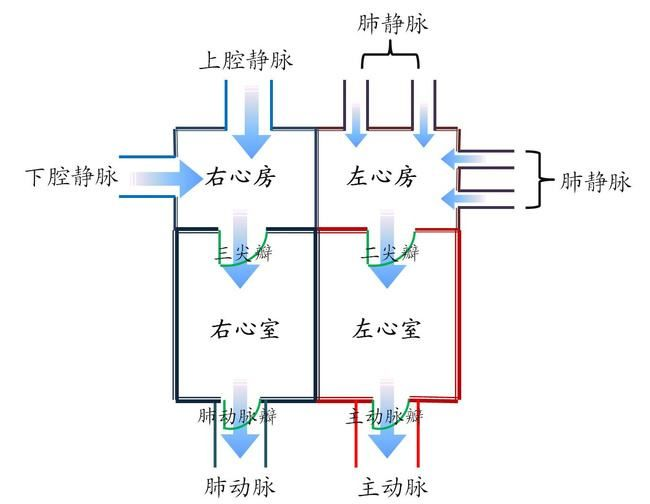

正常的心脏的解剖结构如下图:

可以看到心脏有以下4个心腔(chamber),位于心脏上方的心房(ateria)较小,位于心脏下方的心室(ventricle)较大。

右心房(right atrium):右心房接收来自人体的低氧血液。 -

右心室(right ventricle):右心室将低氧血液泵送至肺部,使肺部充满氧气。 -

左心房(left atrium):左心房从肺部接收富含氧气的血液。 -

左心室(left ventricle):左心室将富含氧气的血液泵送至全身。

为了让血液流入或流出 4 个心腔,

心脏有 4 个瓣膜:

三尖瓣(tricuspid valve):三尖瓣允许缺氧的血液从右心房流向右心室。 -

肺动脉瓣(pulmonary valve):肺动脉瓣将血液从右心室泵入肺部,使血液获得氧气。 -

二尖瓣(mitral valve):二尖瓣使富含氧气的血液从左心房流向左心室。 -

主动脉瓣(mitral valve):主动脉瓣将富含氧气的血液从左心室泵向全身。